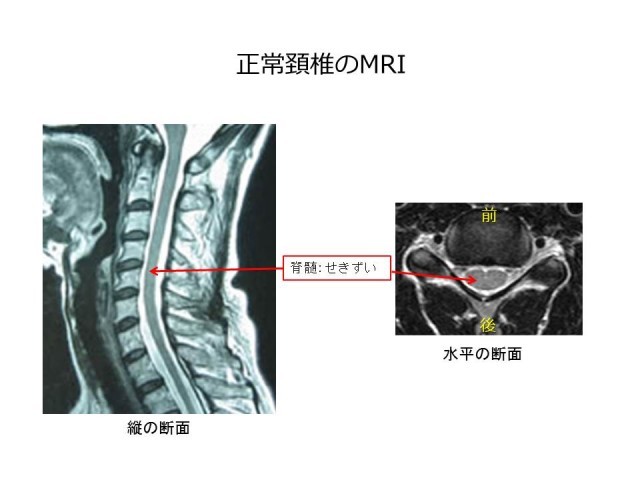

脊髄・脊椎疾患 | 名古屋大学大学院医学系研究科 脳神経外科学, 頚椎脊柱管狭窄症の症例と症状について|白石脊椎クリニック,

頚椎脊柱管狭窄症の症例と症状について|白石脊椎クリニック, 脊椎脊髄センター | 総合東京病院【公式】中野区 練馬区 24時間,